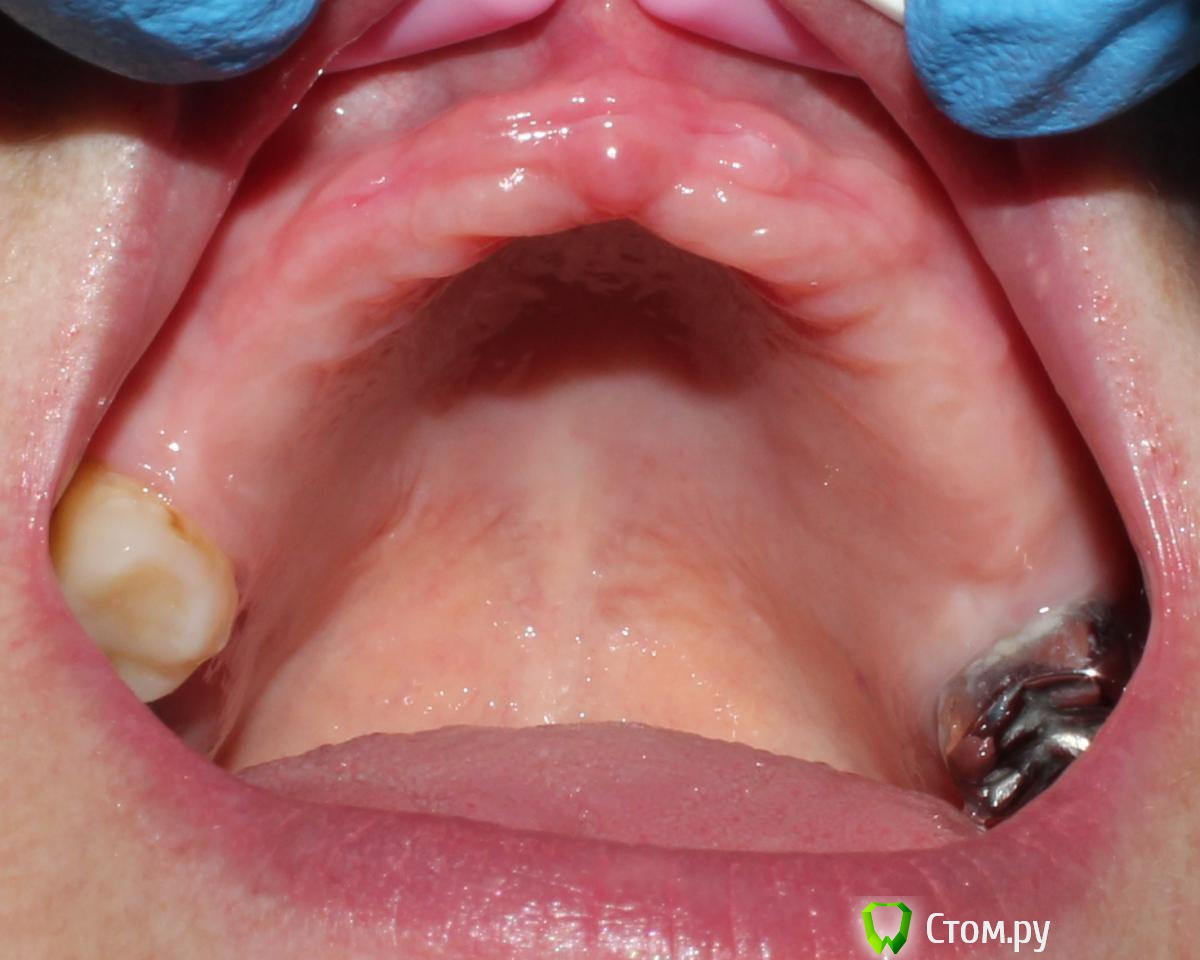

artem29 Опубликовано 19 октября, 2014 Поделиться Опубликовано 19 октября, 2014 (изменено) Уважаемые доктора, поделитесь, пожалуйста, опытом. Есть пациентка, возраст после 40 лет. Желает избавится от частично съёмных протезов, заменить их несъёмными. КТ будет чуть позже.Я (как хирург) могу предположить, что установка имплантатов в позиции 5-5 и 2-2, ждём пока интегрируют и затем балочная конструкция.Перед установкой имплантатов провести синуслифтинг, либо совместить аугментацию и установку имплантатов (решится в процессе синуслифтинга). Слева по типу латерального окна, а справа, возможно, достаточно будет и закрытого. Какую бы тактику спланировали вы на верхней и на нижней челюсти и какой длины имплантаты для верхней челюсти взяли?система: Dentium: SuperLine. Заранее всем благодарен. Изменено 19 октября, 2014 пользователем artem29 Ссылка на комментарий

artem29 Опубликовано 25 октября, 2014 Автор Поделиться Опубликовано 25 октября, 2014 Вот результаты КТ. Воскового планирования пока не было. Сразу несколько вопросов к тему у кого был подобный опыт работ.1. что с инородным телом во 2-ом сегменте? обойти при синуслифтинге, не трогать ту зону с инородным телом или постараться убрать? может нужен лор?2. будут ли состоятельны имплантаты размером 4,5х6,0 в позициях 3.6, 3.7 после нагрузки или нужно проводить аугментацию и ставить имплантаты большего размера? 3. в 4 сегменте предпочтительная аугментация сэндвич-техникой?1 сегмент_1.bmp1 сегмент_2.bmp1 сегмент_3.bmp2 сегмент_1.bmp2 сегмент_2.bmp2 сегмент_3.bmp3 сегмент_1.bmp3 сегмент_2.bmp3 сегмент_3(36).bmp3 сегмент_3(37).bmp Ссылка на комментарий